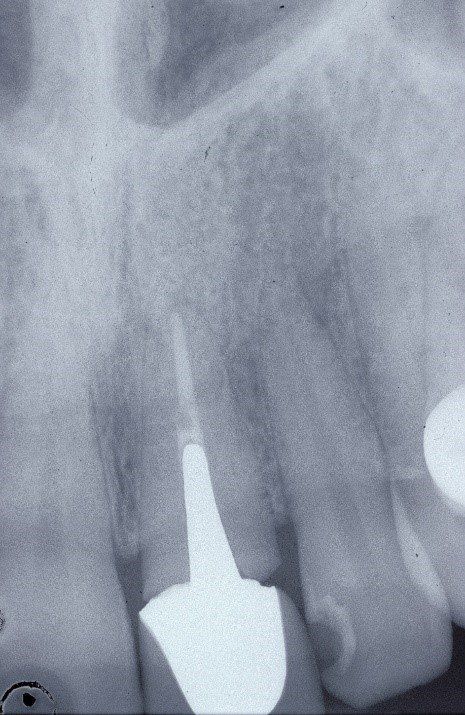

Radiograficamente è visibile il trattamento endodontico dell’incisivo laterale sinistro coinvolto anch’esso nel trauma. Sono visibili inoltre i dispositivi ortodontici necessari pe la sua estrusione al fine di recuperare l’ampiezza biologica, ovvero al fine di mantenere tre millimetri di tessuto dentale sano oltre il margine gengivale

Immagini radiografiche successive è possibile seguire negli anni l’evoluzione del dente reimpiantato. Nel corso degli la radice dell’incisivo centrale è andata in contro ad un progressivo riassorbimento per un atteso fenomeno di anchilosi.

L’anchilosi è un processo biologico infiammatorio che si verifica una volta che le fibre del legamento parodontale sono andate in necrosi e la superficie del cemento che ricompre la radice viene in contatto diretto con l’osso alveolare. In questa circostanza si attiva nei macrofagi una differenziazione in senso osteoclastico e dentino clastico che in pochi anni, talvolta in pochi mesi, porta al completo riassorbimento della radice e quindi alla sua scomparsa

Visione clinica del Maryland bridge cementato con tecnica adesiva ed immagine tomografica tridimensionale per valutare lo spessore bucco palatale utile all’inserimento dell’impianto che fu valutato come sufficiente benchè esiguo. A tal proposito deve essere sottolineato che la letteratura consiglia, quando è disponibile un volume di osso residuo utile all’inserimento di un impianto, di evitare tecniche di innesto osseo in quanto un aumento dei volumi ossei non migliora la prognosi estetica (3)